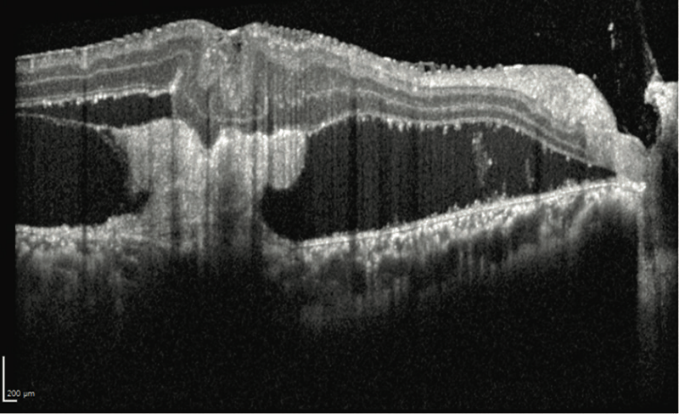

患者为24岁男性,3个月前头部及眼眶多处枪伤,左眼视力无光感,视网膜完全脱离,与晶状体后囊粘连,无法手术;右眼视力20/150。眼前节检查正常;散瞳后检查眼底显示后极部广泛瘢痕,可见视网膜前膜和视网膜下膜(见图2);OCT提示黄斑区视网膜脱离(见图3)。

图3. 右眼OCT提示黄斑区视网膜脱离

Yewlin Chee教授团队对该患者进行了右眼玻璃体切除手术,考虑到患者仅剩右眼有视力,手术使用了25G玻切头。术中,术者通过眼球内注射吲哚菁绿颜料对内界膜染色,更好的辨别视网膜前膜所在平面。向后延伸穿过视网膜进入视网膜下空间的区域,术者使用眼内剪刀在视网膜表面剪断膜,以减少全层破裂的风险。手术保持了视网膜下膜的完整,避免牵引带来的进一步视网膜脱离以及感光细胞的损伤。术后一个月,OCT示视网膜已经复位(见图4),患者右眼视力稳定在20/100。

图4. 一个月后,右眼OCT示视网膜前膜已剥除,视网膜贴平,视力稳定在20/100

本病例为弹伤性脉络膜视网膜炎引发的牵引性视网膜脱离,弹伤性脉络膜视网膜炎是视网膜和脉络膜的全层损伤,可能穿越整个视网膜,必须谨慎剥离。术前需对OCT仔细读片,确认位置并制定手术计划。值得注意的是,在弹伤性脉络膜视网膜炎的瘢痕边缘可能出现裂孔,导致孔源性视网膜脱离。